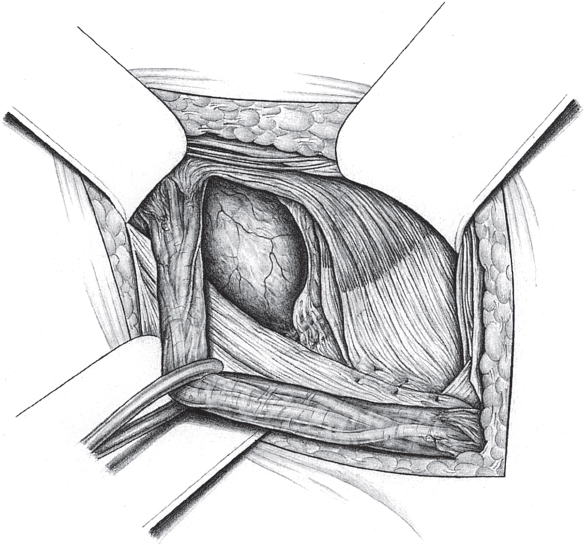

Fig. 3.6 Sliding hernia. It is repaired by creating a new peritoneal ring, incising the free peritoneum.

The presence of a sliding hernia must be suspected if a greatly thickened hernia swelling is found when the external oblique aponeurosis is divided. The hernial sac is dissected in the usual way. It is not necessary to open the sac prior to complete dissection. Adhesions to the spermatic cord can usually be divided readily. The sac of an indirect hernia should be dissected as far as the deep inguinal ring and that of a direct hernia to beneath the level of the transversalis fascia.

If a sliding hernia is suspected based on the consistency of the hernial sac, the sac is opened between clamps on the anterior wall (

Fig. 3.6). It must be ensured that only the anterior peritoneal layer is divided; so, no part of the bowel is injured. Opening the sac of small medial sliding hernias can be omitted when the bladder forms part of the wall. In these cases, a superficial purse string suture suffices to bury the sac.

In the case of larger sliding hernias, the sac must be opened at the lateral and medial border of the sliding component as far as the deep inguinal ring (

Fig. 3.7). This enables the sac contents to be reduced. Reperitonealization should not be attempted because of the risk of injury.

After complete excision of the wall of the hernia bearing the bowel, the free peritoneal margins behind the loop of bowel are sutured to create a new deep inguinal ring (interrupted 2/0 silk or PDS suture;

Fig. 3.8). The hernia contents can then be reduced.